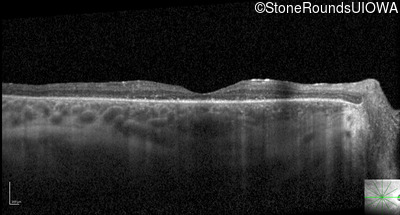

Optical Coherence Tomography - Left - 20/50

Exemplar / OCT Stack

OCT Stack